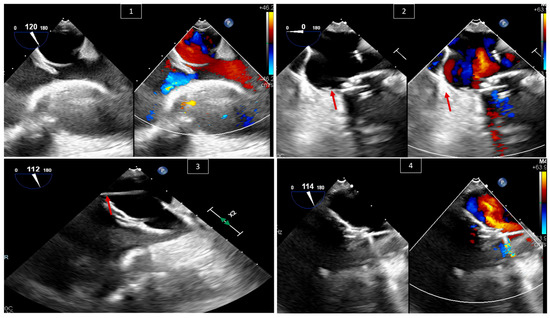

4. Transcatheter Edge-to-Edge Repair (TEER) of Systemic AV Valve